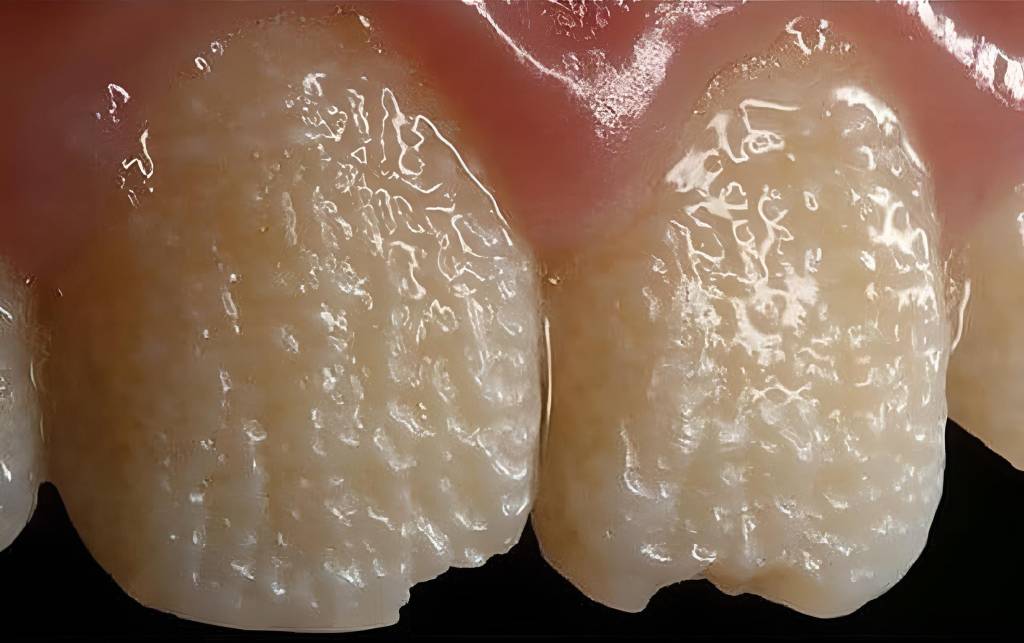

Essa alteração compromete a estrutura e a qualidade da dentina, resultando em dentes com aspecto opalescente, coloração variando entre acinzentada, amarelada e marrom, além de maior fragilidade mecânica.

Diferente da amelogênese imperfeita, na DI o esmalte está presente inicialmente de forma normal, mas a dentina subjacente defeituosa compromete a adesão e a resistência geral do dente, levando ao desgaste precoce.

- Alteração de cor: dentes opalescentes, acinzentados ou amarronzados.

- Redução da espessura dentinária: levando à alteração da translucidez do dente.